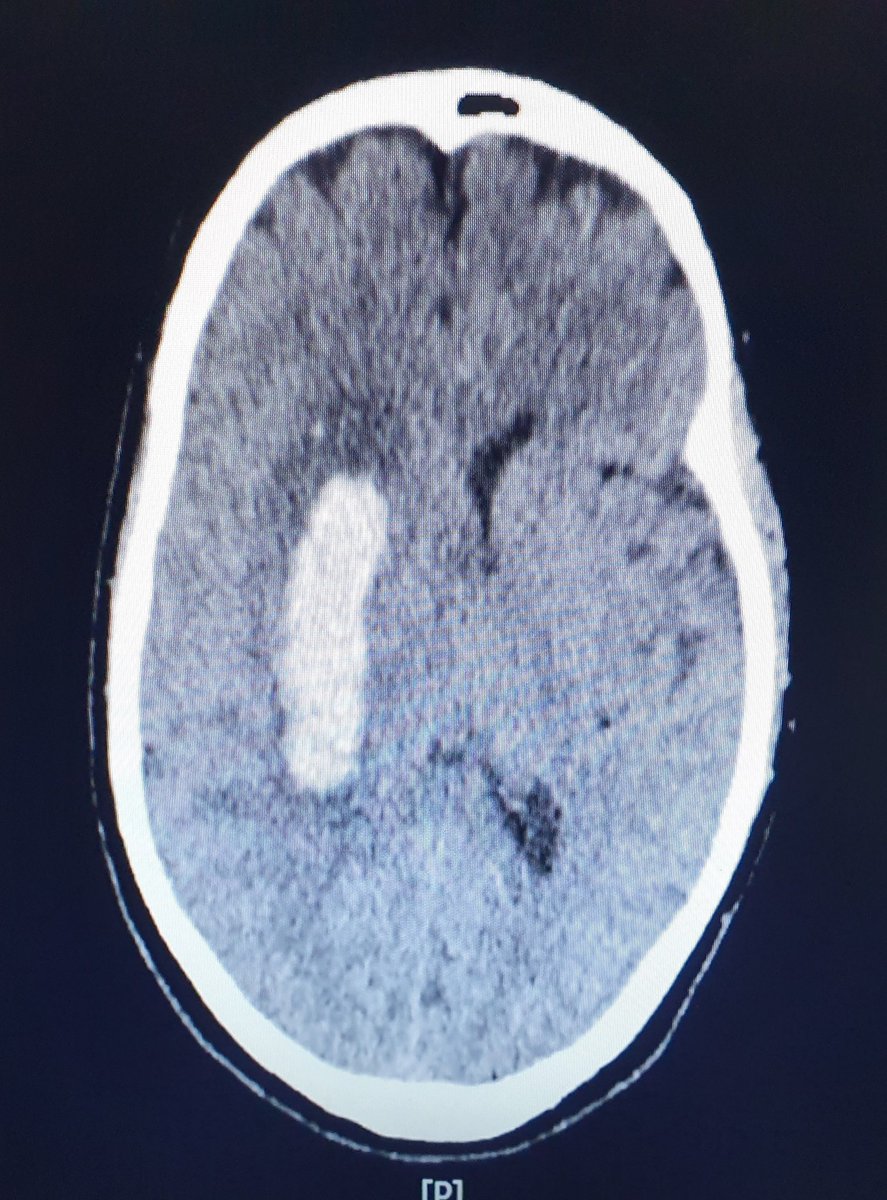

CT Brain tu tunjuk yang dah berlaku pendarahan dalam otak sebab tekanan darah yang terlalu tinggi.

Salur darah dah pecah.